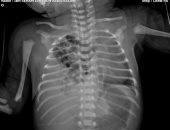

جراحة نادرة تنقذ حياة طفل من فتق بالحجاب الحاجز بمستشفى زاوية الناعورة

الخميس، 23 أكتوبر 2025 05:47 م

فى إنجاز طبى جديد يُضاف إلى سجل النجاحات المتميزة لقطاع الصحة بالمنوفية، نجح الفريق الجراحى بمستشفى زاوية الناعورة المركزى بقيادة الدكتور مجدى لولح..